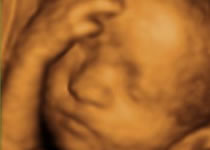

Útero, ovarios y niño no nato (feto) en pacientes embarazadas